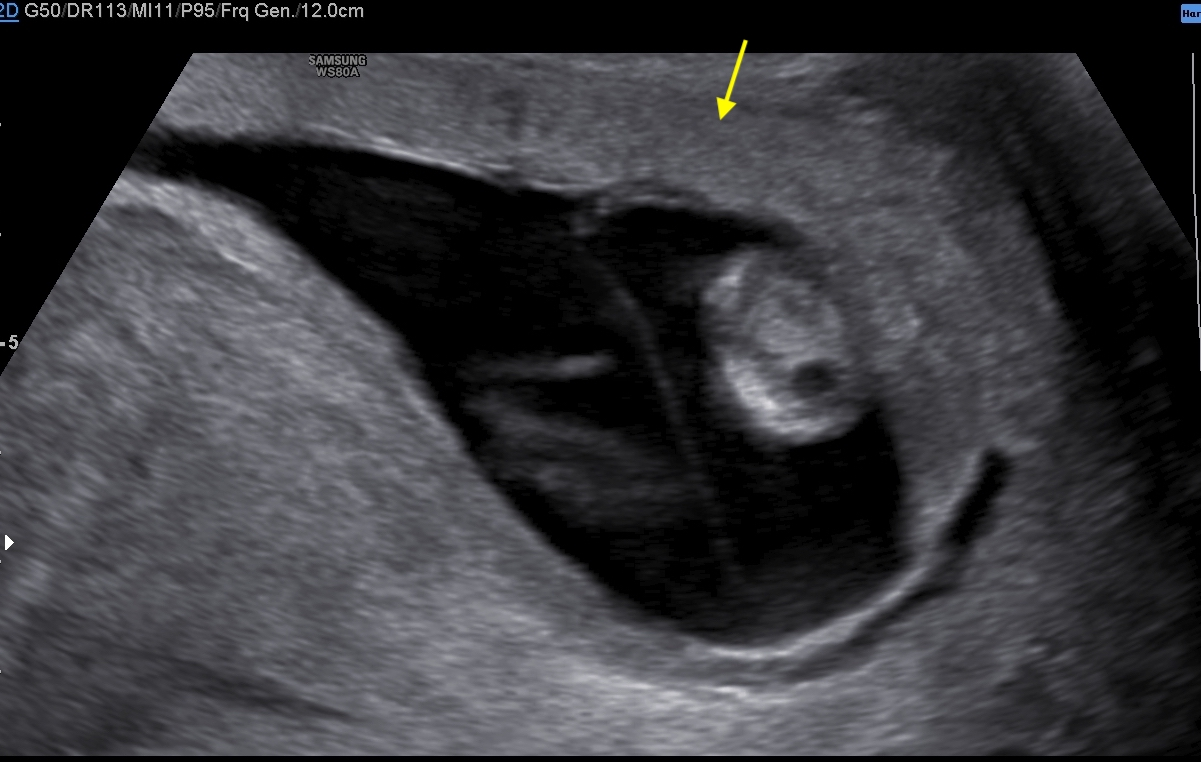

A healthy 39-year-old woman G4P3 was admitted to our high-risk pregnancy outpatient service due to a MC-DA twin pregnancy. Monochorionicity was suspected by the referring gynecologist during the dating ultrasound scan (US). The nuchal translucency US at the 12th week of gestation highlighted a “T” sign of the dividing membrane with a unique anterior placenta confirming a MC-DA twin pregnancy, as shown in Fig. 1. Soft markers for trisomy were found to be normal for both twins. The US performed during the 14th week of gestation showed the twins significantly closer to each-other standing on the same side of a free-floating thin membrane inserted on the placenta. This image raised the suspicion for a spontaneous septostomy (Fig. 2). The patient underwent amniocentesis as the combined serum screen showed an increased risk for Trisomy 21. US assisted invasive procedure did not detect the dividing membrane deposing for a PMM twin pregnancy following SS. A single sample of amniotic fluid was obtained and tested normal for fetal karyotype (46, XX). According to International Guidelines US imaging was performed every two weeks. Anomaly scan was normal and all subsequent Doppler US showed a normal twin growth and fetal wellbeing until the early third trimester [14, 15, 16]. The US performed at the 27th week of gestation showed a strict contiguity of the umbilical cords with a suspicion for cord entanglement on 3-dimensional (3D) US (Fig. 3A,B). The patient was hospitalized for close pregnancy surveillance. Fetal heart monitoring and US scan were daily performed. Steroids were administered for prevention of respiratory distress syndrome. The 29th week US scan highlighted a growth discordance ranging around 21% (symmetric growth at the 71° centile (estimated weight: 1328 gr) and at the 36° centile (estimated weight: 1043 gr) for Twin A and Twin B respectively). An episode of prolonged bradycardia was registered for Twin A. An emergency cesarean section was performed: two healthy girls were born (Twin A: weight 1360 gr, Apgar 4 and 7 at 1st and 5th minute respectively — Twin B: weight 1000 gr, Apgar 8 and 9 at 1st and 5th minute respectively). Cord entanglement was confirmed as shown in Fig. 4. The mother’s postoperative recovery was uneventful. Twins’ developmental follow-up at 12 months of age was normal.

Fig. 2.Sonogram depicting a thin free-floating membrane inserting on a unique anterior placenta with the two twins standing close to each other on the same side of the membrane.